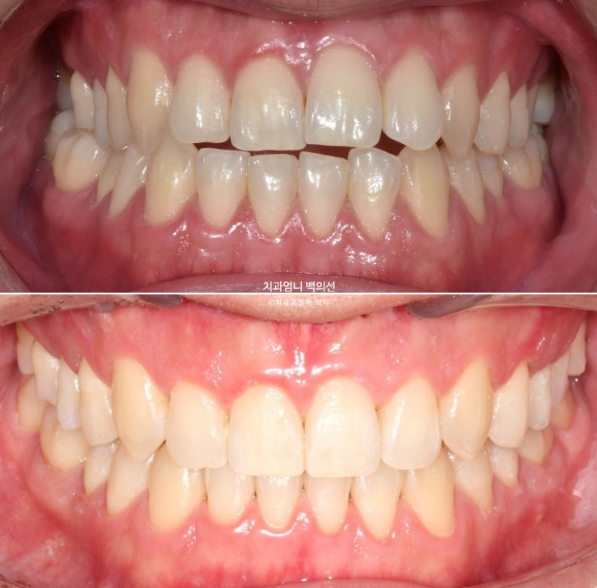

Now let’s compare before and after.

Treatment began in January 2023, and the time spent on arch expansion and waiting for bone to fill in was 6 months. The actual orthodontic treatment period while wearing Invisalign aligners was from July 2023 to March 2025, for a total of 1 year and 8 months.

The upper arch widened through the palatal expansion device

In the front teeth area, once the open bite and reverse bite were corrected, a stable bite was created.